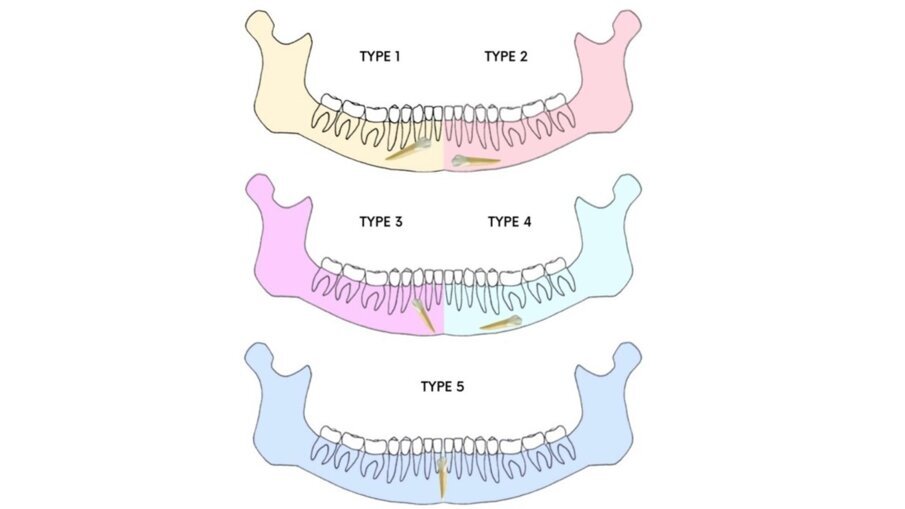

L’eruzione alterata di un canino mandibolare può portare a due condizioni cliniche che possono essere combinate: l’inclusione e la trasmigrazione. Il dente incluso può occasionalmente rimanere nella stessa emiarcata o migrare lateralmente attraverso un fenomeno chiamato trasmigrazione3. L’incidenza dei canini mandibolari inclusi (CMI) e trasmigrati ha una prevalenza compresa tra 0,05% e 0,4%. I canini mandibolari e mascellari rivestono un ruolo fondamentale nel mantenimento della forma e della funzione dell’arcata, ed il mancato recupero dei canini inclusi può comportare il riassorbimento o la migrazione delle radici vicine, la perdita della forma dell’arcata naturale e la formazione di cisti dentigere4. Secondo la classificazione di Mupparapu (Fig. 1), i CMI sono classificati in cinque tipi, di cui il tipo 1 è il più frequente5. La diagnosi precoce consente di valutare l’entità della trasmigrazione canina e ridurre le complicanze estetiche e funzionali6-10.

Fig. 1_Classificazione di Mupparapu.